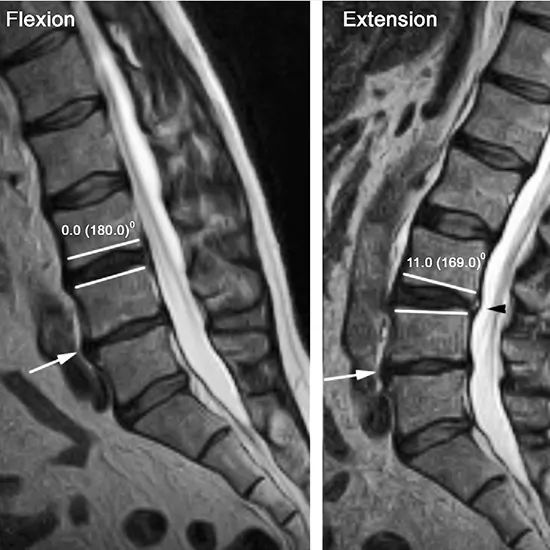

The lumbar Spine extension position is the bending backward of the spine. MRI LS (lumbosacral) spine Extension is an imaging procedure used to view the lumbar spine to identify the dynamic changes in the diameter of the spinal canal, nerve compression, disc displacement, and vertebral stability.

• Retrolisthesis (Backward slippage of vertebrae)